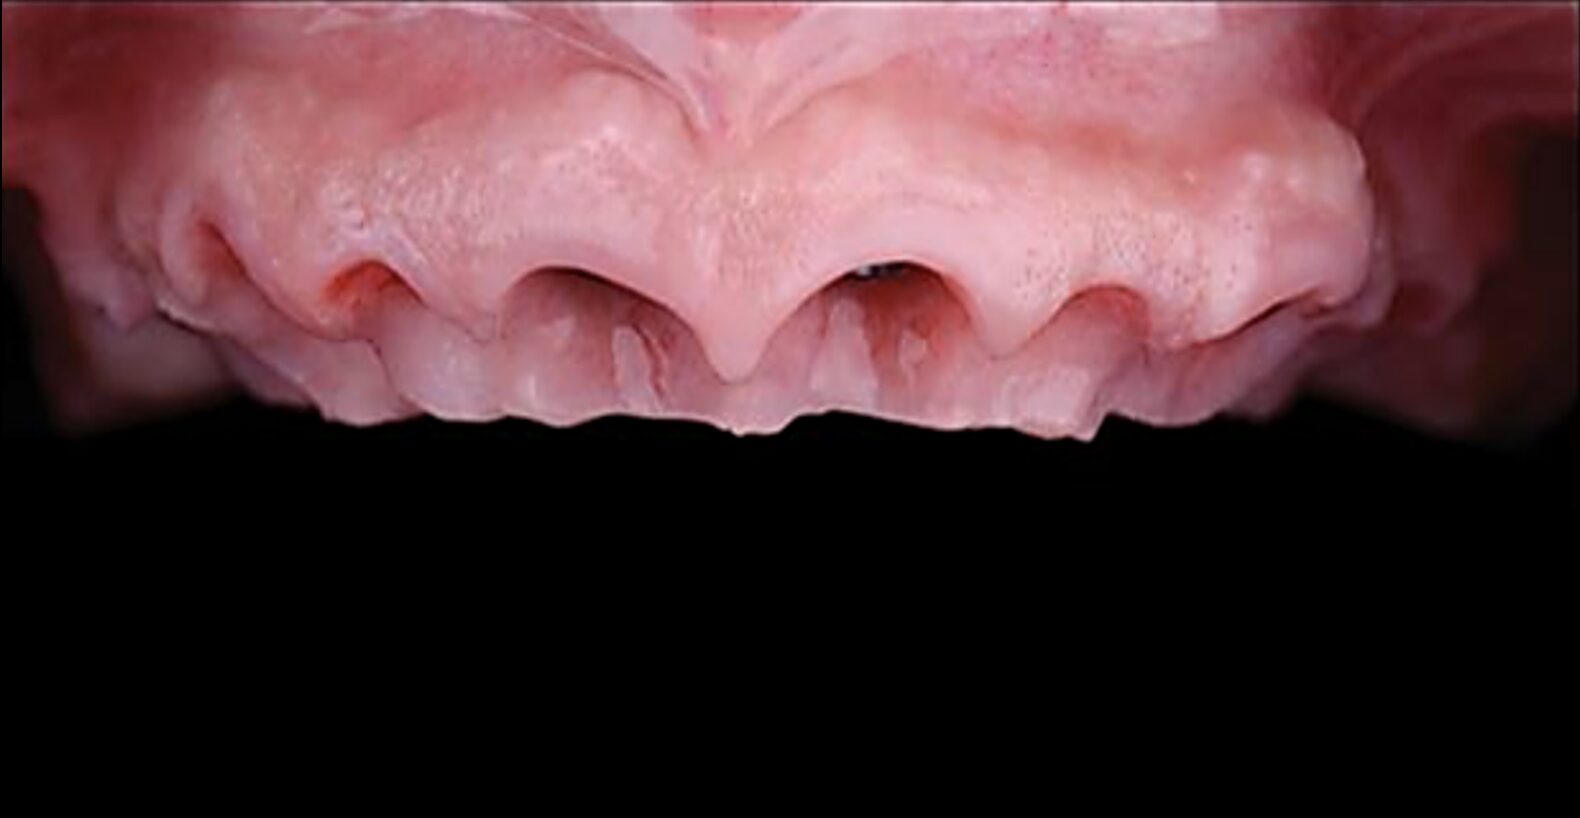

Cas clinique « GOLD DAMAGE CONTROL MCI » maxillaire : Bridge implanto-porté avec extensions postérieures (ALL ON 8). Version définitive des bridges avec un cosmétique en céramique.

Cas clinique « GOLD DAMAGE CONTROL MCI » maxillaire : Bridge implanto-porté avec extensions postérieures (ALL ON 10). Version définitive des bridges avec un cosmétique en céramique.